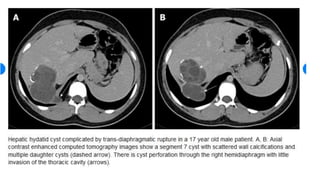

• Hepatic hydatid cyst

• Presentation

• Abdominal

• pain